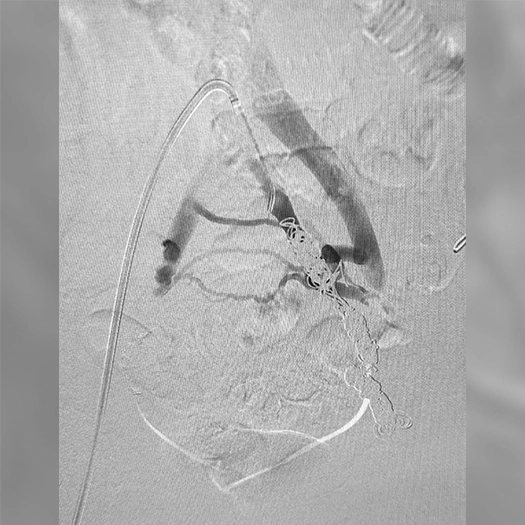

Coiling off left internal iliac vein draining into a common truck in the caval bifurcation

Ruby® XL Dr. Manuel Perez AdventHealth Orlando, FL

Zoomed in view of Ruby XL Detail

Coils Used: 12mm x 55cm POD XL, 70cm Packing Coil XL, 8mm x 70cm POD XL

Catheter: 6.5F Destino Sheath and 5F 100cm Kumpe